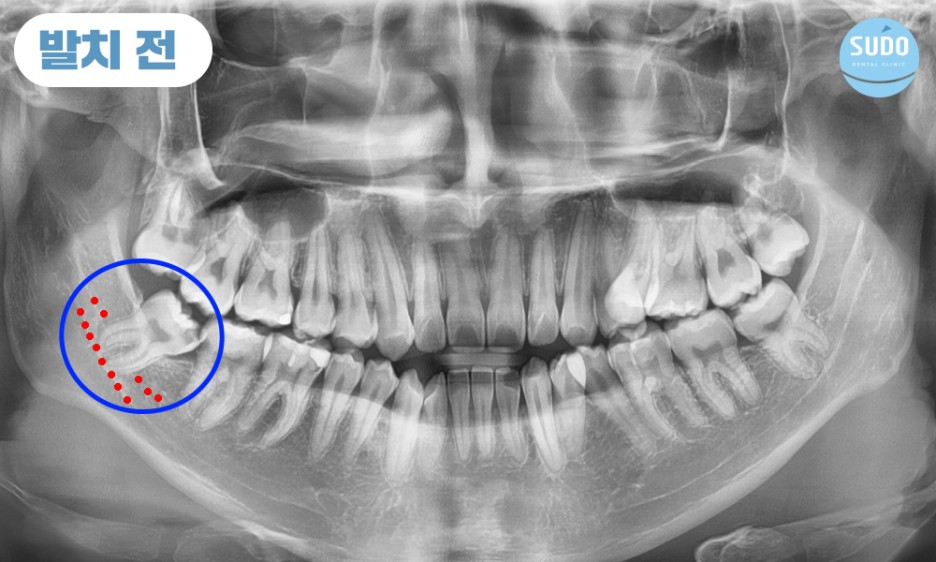

본 환자분은 20대 초반의 남성분으로 오른쪽 아래 매복되어 있는 사랑니에 충치가 심하게 진행되어 치아 일부가 이미 파절된 상태로 본원에 내원해 주셨습니다.

X-ray를 촬영해 보니 치아 뿌리 끝이 신경관과 매우 근접한 상태였습니다. 신경관 손상 가능성이 있어 까다로운 케이스였는데, CT로 촬영하여 정밀 분석한 결과를 토대로 환자분의 충분한 상담을 통해 발치를 진행하기로 했습니다.

파노라마 사진에서 보이는 것과 같이 아래쪽 어금니 아래는 많은 신경들이 지나갑니다.

발치를 하다가 신경을 잘못 건드릴 위험이 있기 때문에 정밀한 진단이 가능한 3차원 영상 장비를 갖추고 있는지, 풍부한 임상경험과 노하우를 겸비한 의료진이 상주하고 있는지 확인하는 것이 중요합니다.